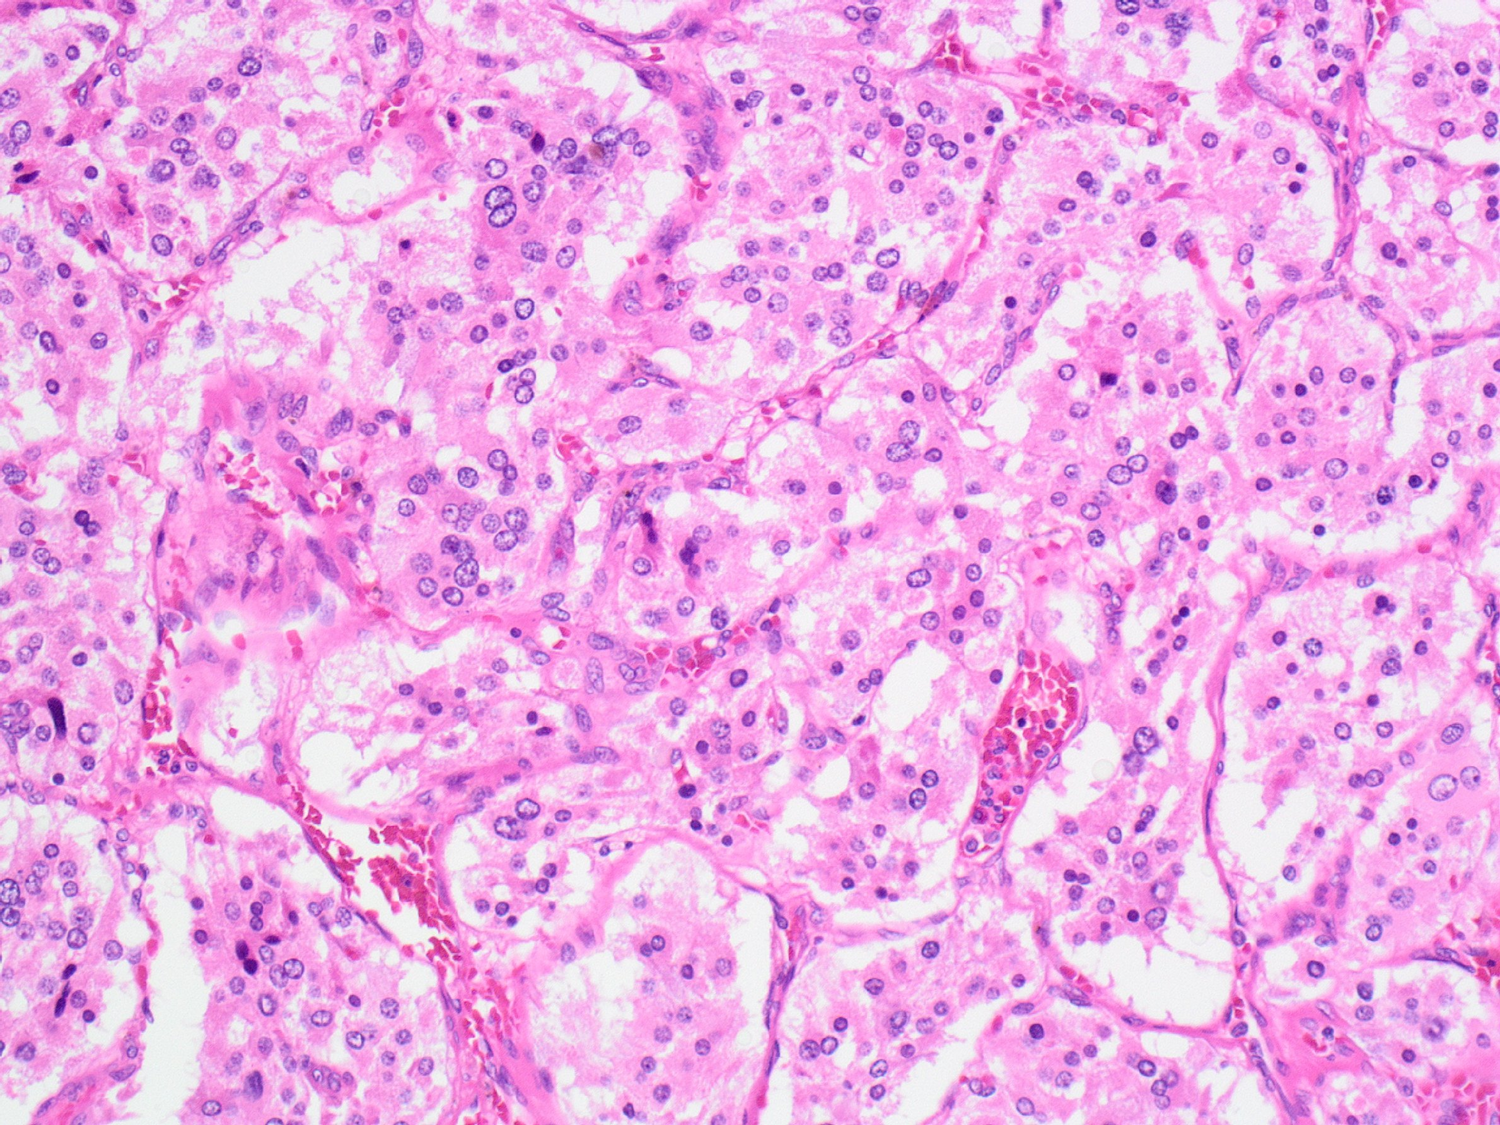

What are the histological features of pheochromocytoma?

Pheochromocytoma are identified on histology by Zellballen patterns

→ tumor cells arranged in a nested/zellballen architecture and separated by stroma

1) Also have salt and pepper chromatin within the nuclei due to its origin as a neuroendocrine neoplasm